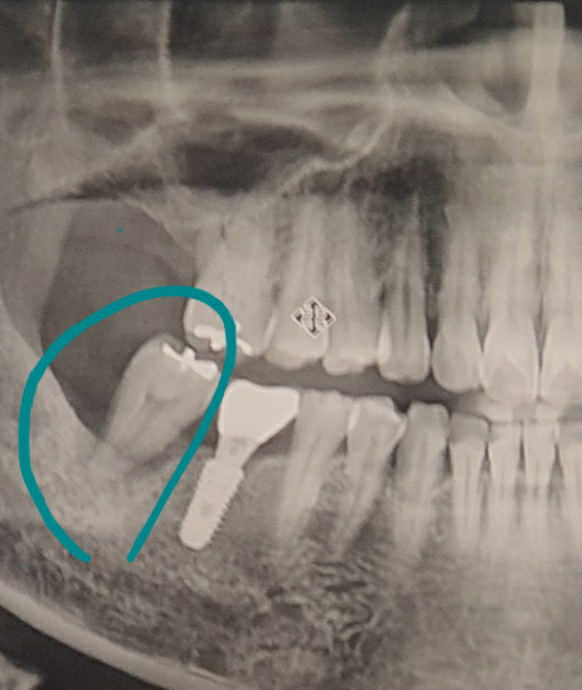

동그라미친 저치아가 흔들리는데 치과에서 뽑아야한다고 합니다. 이럴경우

1. 뽑은치아부분 즉 아래치아 임플란트만 하면 될까요.

2. 아래와 그위쪽 끝부분 비어있는곳도 임플란트를

해야할까요. (위쪽치아는 대략 9년정도전에 발치하고

그때 선생님께서 위쪽은 임플란트 필요없다해서

안했었거든요. )

3. 그냥 아래 발치하고 아래위 다 임플란트 안하고

없는상태로 살아도 될까요

• 1번 째 사진